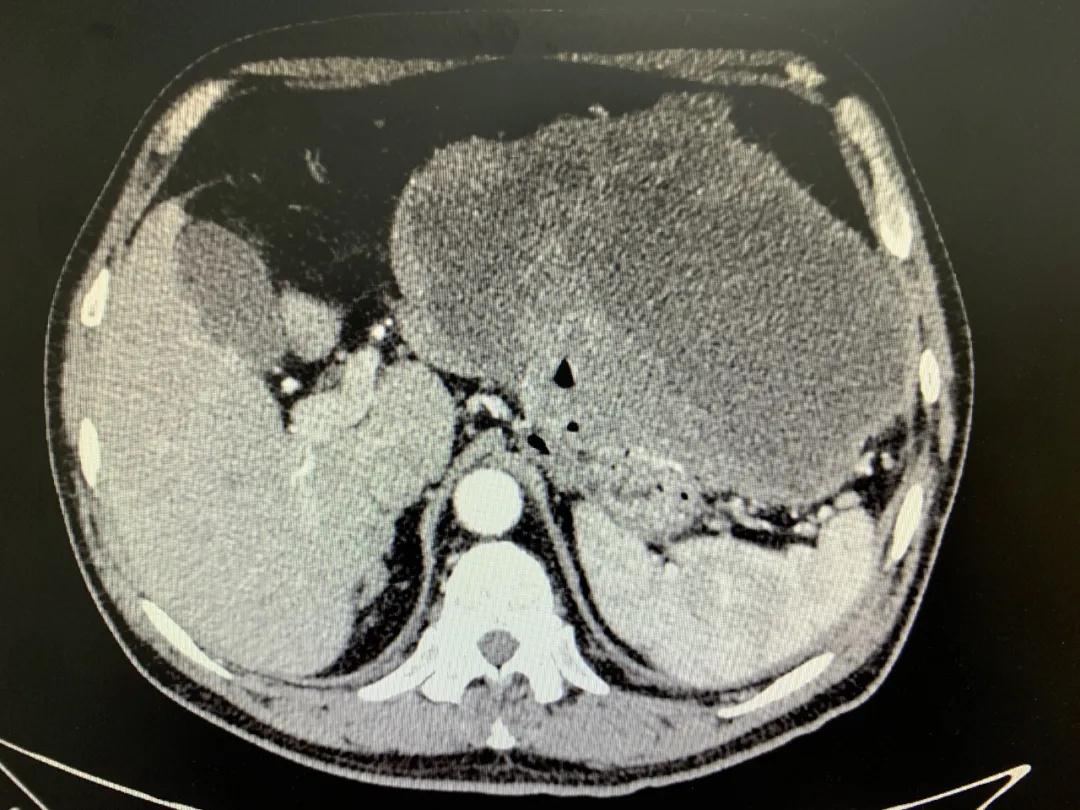

患者入院時(shí)血紅蛋白數(shù)值仍持續(xù)下降,出現(xiàn)失血性休克表現(xiàn),危及生命。消化外科二病區(qū)蔡磊主任接診后,組織科室迅速對(duì)患者進(jìn)行了全面的檢查。CT提示腫瘤大小約19.3*10.3cm,腫瘤內(nèi)提示大量積血。結(jié)合相關(guān)檢查,考慮為罕見(jiàn)的巨大胃間質(zhì)瘤合并出血。